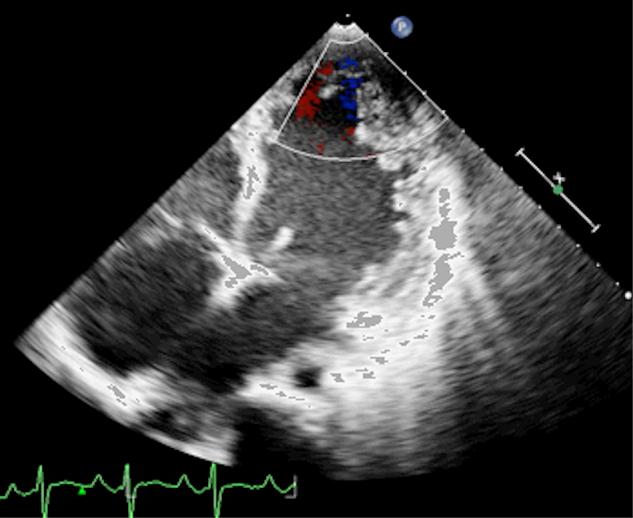

Isolated ventricular noncompaction (IVNC) is an unclassified cardiomyopathy characterized by prominent intraventricular trabeculations separated by deep intertrabecular recesses. Although microvascular dysfunction is known, myocardial infarction is rare and usually seen as a consequence of coincidental coronary artery disease. We report the case of a 19-year-old male patient who presented to us with symptoms and signs of heart failure. Echocardiography revealed IVNC with severe left ventricular dysfunction. He was put on medical treatment including oral anticoagulants. Six months later, he came to our emergency department with anterior wall STEMI. Coronary angiogram revealed thrombotic occlusion of distal LAD, which resolved completely with tirofiban and heparin. Coronary thromboembolism due to blood stasis in the left ventricular cavity has not been previously documented in IVNC.

孤立性心室肌致密化不全(IVNC)是一种未分类的心肌病,其特征为显著的心室小梁,被深的小梁间隐窝分隔。虽然已知微血管功能障碍,但心肌梗死罕见,通常是巧合的冠状动脉疾病的结果。我们报告一例19岁男性患者,他因心力衰竭的症状和体征前来就诊。超声心动图显示IVNC伴严重左心室功能障碍。他接受了包括口服抗凝剂在内的药物治疗。六个月后,他因前壁ST段抬高型心肌梗死来到我们的急诊科。冠状动脉造影显示左前降支远端血栓性闭塞,替罗非班和肝素治疗后完全缓解。IVNC中因左心室腔内血液淤滞导致的冠状动脉血栓栓塞此前未见报道。